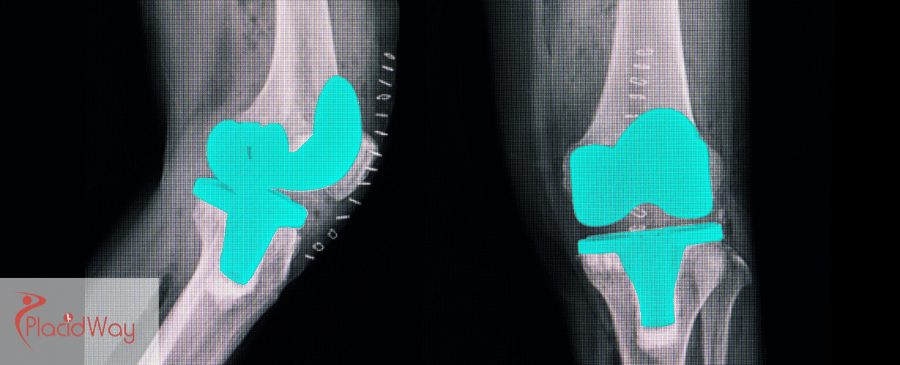

Knee replacement surgery, or knee arthroplasty, is a surgical procedure to resurface a knee damaged by arthritis, injury, or wear and tear. The goal is to relieve pain and restore function.

An orthopedic surgeon replaces damaged bone and cartilage with a prosthetic joint made of metal and plastics. Whether total (TKR) or partial (PKR), knee replacement is among the most successful surgeries, restoring mobility and quality of life.